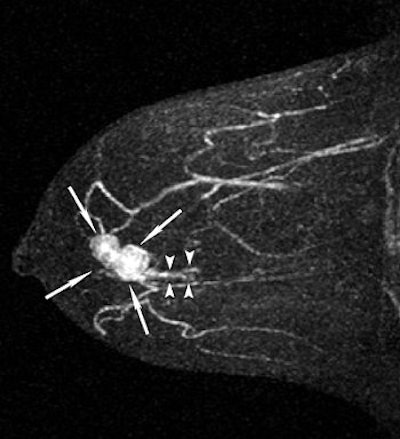

![]() |

| A 43-year-old woman with invasive ductal carcinoma in right breast. Above, maximum intensity projection (MIP) image of MDCT images reveals location of main tumor (arrows) but not intraductal component. Below, MIP image of MRI reveals a clumped enhancement (arrowheads) distal to main tumor (arrows), which was suspected to be intraductal component. Intraductal component distal to main tumor was confirmed on histopathologic examination. Shimauchi A, Yamada T, Sato A, Takase K, Usami S, Ishida T, Moriya T, and Takahashi S, "Comparison of MDCT and MRI for Evaluating the Intraductal Component of Breast Cancer" (AJR 2006; 187:322-329). |

Based on histopathology results, the majority of the tumors (63) were invasive ductal carcinoma and 44 of these had an intraductal component. Two radiologists reviewed the images in consensus, taking into consideration the distribution pattern of lesion enhancement and the morphologic typing of invasive tumors.

All 69 cases of invasive carcinoma were depicted on MDCT and MR images. The sensitivity of CT for detecting an intraductal component was 61%. Its specificity was 88% and the accuracy was 71%. In comparison, MR's sensitivity came in at 75%, its specificity at 88%, and its accuracy at 80%. In six patients, intraductal components were seen on MRI but not on CT. Both modalities missed intraductal components in 11 cases.

"There were no cases in which MDCT revealed an intraductal component that was undetectable with MRI," the authors stated. "The greater contrast obtained with MRI by using the subtraction technique probably contributed to the higher sensitivity of this method."

In terms of the morphologic typing of tumors, both modalities generally underestimated the length of the intraductal component. The correlation co-efficient between the length of the main tumor on MDCT and histopathology was 0.72 versus 0.70 for MRI. However, "underestimation of the length of the intraductal component by 15 mm or more was significantly less frequent with MRI than with MDCT," the group wrote.